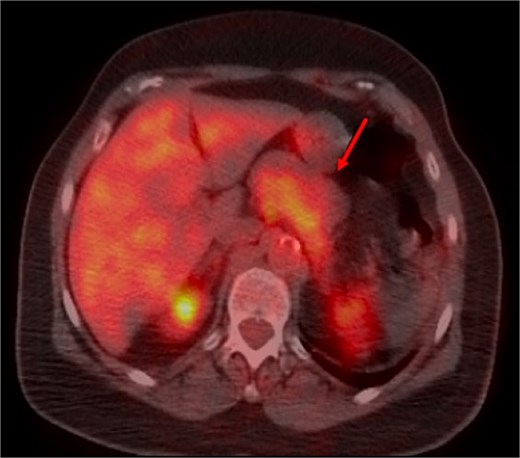

A thoraco-abdominopelvic computed tomography (CT) scan performed for staging revealed a well-defined, homogeneous soft-tissue mass anterior to the celiac trunk, superior to the pancreas, and medial to the stomach (Fig. 1). A positron emission tomography (PET) scan confirmed the previously known hypermetabolic retroareolar lesion of the right breast and revealed a large hypermetabolic mass in the celiac–mesenteric region, measuring 63 × 35 × 50 mm (Fig. 2). An abdominal MRI characterized the mass as a well-defined 6-cm lesion with mixed solid and cystic signal intensity, closely related to the celiac trunk, pancreas, stomach, and left adrenal gland (Fig. 3). Biochemical testing showed elevated urinary normetanephrine and metanephrine levels, consistent with catecholamine hypersecretion.